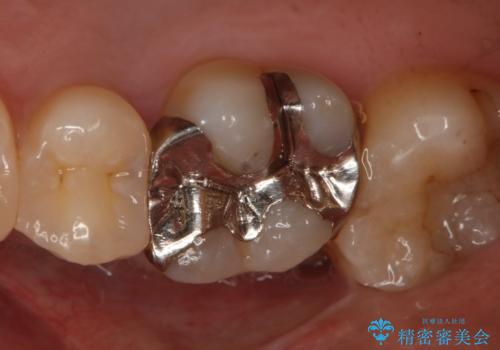

- 右上6番の銀歯をセラミックに変えたいと希望された患者様です。

切削量、形態を考慮し、セラミックインレーでの治療を計画しました。

銀歯と虫歯を除去した上でCRで裏層し形態を整えて印象を行っています。